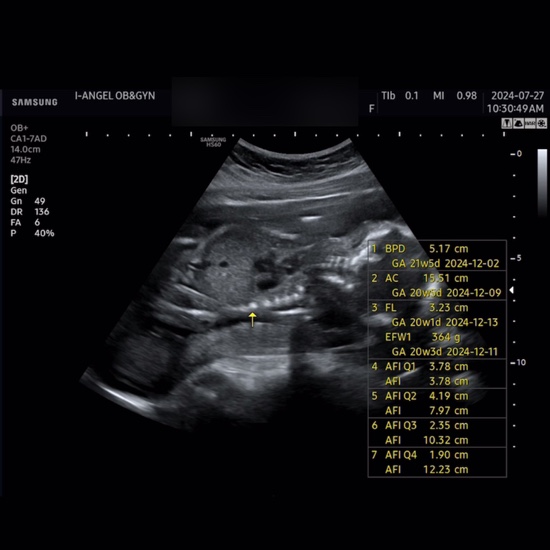

다낭성 난소 증후군 임신 기록 #15 16주차~20주차 2차기형아검사 및 정기검진 취약X증후군

다낭성 난소 증후군 임신기록 15 임신 20주차 입성!! 16주차~20주차 기록❤️ 어느덧 임신 20주차에 들어섰...